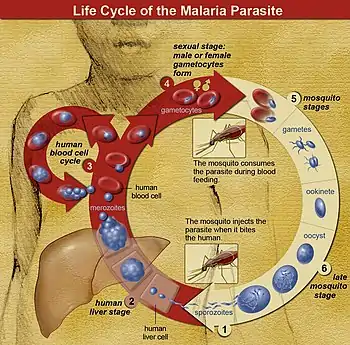

The Anopheles mosquitos initially get infected by Plasmodium by taking a blood meal from a previously Plasmodium infected person.[39][40] Parasites are then typically introduced by the bite of an infected Anopheles mosquito. Some of these inoculated parasites, called "sporozoites", probably remain in the skin,[41] but others travel in the bloodstream to the liver, where they invade hepatocytes.[42] They grow and divide in the liver for 2–10 days, with each infected hepatocyte eventually harboring up to 40,000 parasites.[42] The infected hepatocytes break down, releasing this invasive form of Plasmodium cells, called "merozoites" into the bloodstream. In the blood, the merozoites rapidly invade individual red blood cells, replicating over 24–72 hours to form 16–32 new merozoites.[42] The infected red blood cell lyses, and the new merozoites infect new red blood cells, resulting in a cycle that continuously amplifies the number of parasites in an infected person.[42] Over rounds of this infection cycle, a small portion of parasites do not replicate, but instead develop into early sexual stage parasites called male and female "gametocytes". These gametocytes develop in the bone marrow for 11 days, then return to the blood circulation to await uptake by the bite of another mosquito.[42] Once inside a mosquito, the gametocytes undergo sexual reproduction, and eventually form daughter sporozoites that migrate to the mosquito's salivary glands to be injected into a new host when the mosquito bites.[42]

The liver infection causes no symptoms; all symptoms of malaria result from the infection of red blood cells.[33] Symptoms develop once there are more than around 100,000 parasites per milliliter of blood.[33] Many of the symptoms associated with severe malaria are caused by the tendency of P. falciparum to bind to blood vessel walls, resulting in damage to the affected vessels and surrounding tissue. Parasites sequestered in the blood vessels of the lung contribute to respiratory failure. In the brain, they contribute to coma. In the placenta they contribute to low birthweight and preterm labor, and increase the risk of abortion and stillbirth.[33] The destruction of red blood cells during infection often results in anemia, exacerbated by reduced production of new red blood cells during infection.[33]

Pathophysiology

Malaria infection develops via two phases: one that involves the liver (exoerythrocytic phase), and one that involves red blood cells, or erythrocytes (erythrocytic phase). When an infected mosquito pierces a person's skin to take a blood meal, sporozoites in the mosquito's saliva enter the bloodstream and migrate to the liver where they infect hepatocytes, multiplying asexually and asymptomatically for a period of 8–30 days.[51]

After a potential dormant period in the liver, these organisms differentiate to yield thousands of merozoites, which, following rupture of their host cells, escape into the blood and infect red blood cells to begin the erythrocytic stage of the life cycle.[51] The parasite escapes from the liver undetected by wrapping itself in the cell membrane of the infected host liver cell.[52]

Within the red blood cells, the parasites multiply further, again asexually, periodically breaking out of their host cells to invade fresh red blood cells. Several such amplification cycles occur. Thus, classical descriptions of waves of fever arise from simultaneous waves of merozoites escaping and infecting red blood cells.[51]

Some P. vivax sporozoites do not immediately develop into exoerythrocytic-phase merozoites, but instead, produce hypnozoites that remain dormant for periods ranging from several months (7–10 months is typical) to several years.[48] After a period of dormancy, they reactivate and produce merozoites. Hypnozoites are responsible for long incubation and late relapses in P. vivax infections,[48] although their existence in P. ovale is uncertain.[53]

The parasite is relatively protected from attack by the body's immune system because for most of its human life cycle it resides within the liver and blood cells and is relatively invisible to immune surveillance. However, circulating infected blood cells are destroyed in the spleen. To avoid this fate, the P. falciparum parasite displays adhesive proteins on the surface of the infected blood cells, causing the blood cells to stick to the walls of small blood vessels, thereby sequestering the parasite from passage through the general circulation and the spleen.[54] The blockage of the microvasculature causes symptoms such as those in placental malaria.[55] Sequestered red blood cells can breach the blood–brain barrier and cause cerebral malaria.[56]